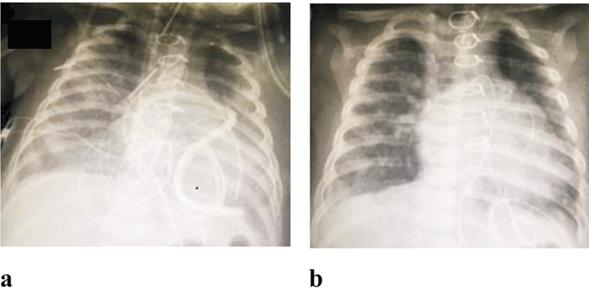

Figura 1: Radiografía de tórax de los casos 3 (a) y 4 (b) donde se evidencia la opacidad inhomogénea pulmonar secundario al pasaje de sangre al intersticio pulmonar y al espacio alveolar. Radiográficamente no es posible distinguir dicho patrón de otras causas de infiltrado intersticial o consolidación alveolar (por ejemplo, edema pulmonar, neumonía, etcétera).

Lactante de 5 meses. Coartación de aorta y comunicación interventricular amplia. En el período neonatal se realiza reparación de coartación y cerclaje de tronco de arteria pulmonar. En la evolución alejada se constata cerclaje ajustado que determina hipoflujo pulmonar con tendencia a la desaturación. Nueva cirugía a los cinco meses con cierre de CIV y retiro de cerclaje en arteria pulmonar. Cursa posoperatorio inicialmente sin eventos, estabilidad hemodinámica y respiratoria. Extubación coordinada a las tres horas de reingreso, drenaje quirúrgico mediastinal con gasto bajo de sangre. Radiografía de tórax (RxTx) posextubación se constata edema pulmonar (Figura 1a). Tendencia a la desaturación y trabajo respiratorio en aumento, a las 24 horas IOT y AVM. Sangrado severo por vía aérea, parámetros ventilatorios elevados y reposición de hemoderivados. Ecocardiograma no evidencia lesiones residuales con buena función sistólica biventricular. Paciente fallece a las 48 horas del posoperatorio. Estudio anatomopatológico confirma presencia de HAD y gran coágulo perihe pático por pasaje inadvertido de sangre a peritoneo.

Lactante de 6 meses. Síndrome de Down y canal atrioventricular (AV) completo. Posoperatorio inmediato de reparación de canal AV con extubación a las 6 horas de la intervención quirúrgica. En las primeras 24 horas trabajo respiratorio que requiere IOT y AVM, soplo holo sistólico a la auscultación. RxTx evidencia edema pulmonar (Figura 1b). Sangrado en vía aérea que se controla con incremento de parámetros ventilatorios y reposición de hemoderivados. Ecocardiograma posoperatorio constata insuficiencia valvular severa a izquierda con fracción de eyección de ventrículo izquierdo conservada. A la semana de la cirugía se reinterviene reparando insuficiencia valvular, alta a domicilio a los 15 días con requerimiento de oxígeno durante 30 días.